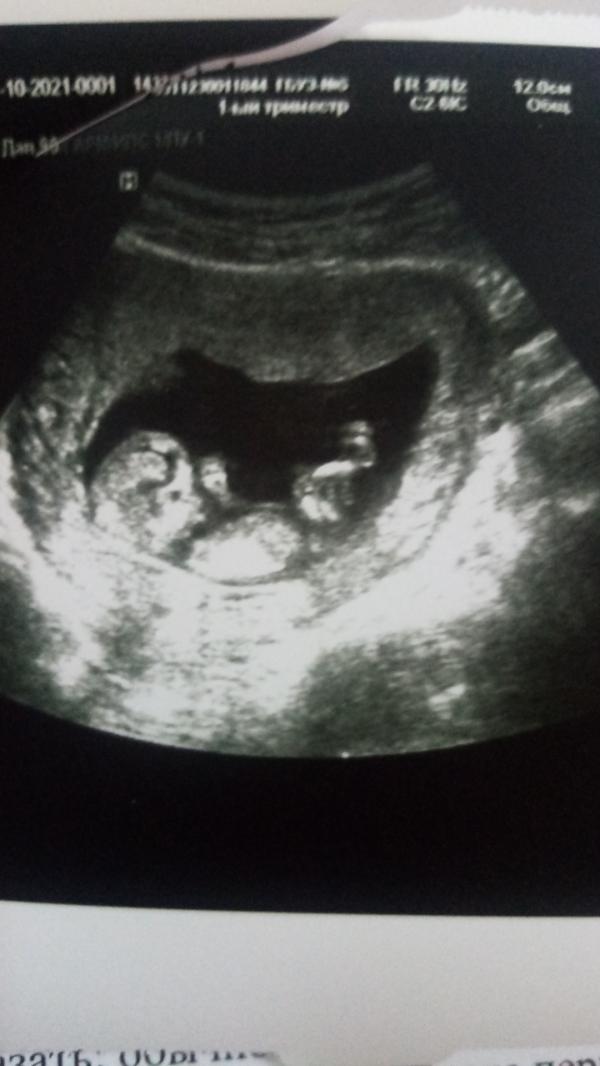

Всем привет, я тут новенькая. Наконец-то то могу насладиться беременностью, расслабиться и не думать о плохом) начало было страшным, 2 раза на сохранении и 2 гематомы большого размера. Боялась шевелиться и резко повернуться, спать не могла. И вот наконец то все хорошо)